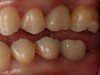

Fig 16. Final crown No. 19 delivered.

Figure 16

Integrative digital planning can also lead to quicker and more efficient treatment times for dental implant therapy. Another patient presented for a dental implant to replace tooth No. 19 at the end of orthodontic treatment. By leveraging 3D planning (Figure 13) and the printing of a surgical guide, the patient's implant was placed using a flapless approach. At the time of placement, an intraoral scan body was placed on the implant and digital impressions were made for her final restoration (Figure 14). At 10 weeks, the final custom abutment and CAD/CAM crown were delivered, all digitally fabricated without the use of physical models (Figure 15 through Figure 17). For implant placement and restoration, the patient had two visits, with a total chair time of 65 minutes, and no need for anesthetic at the second visit.